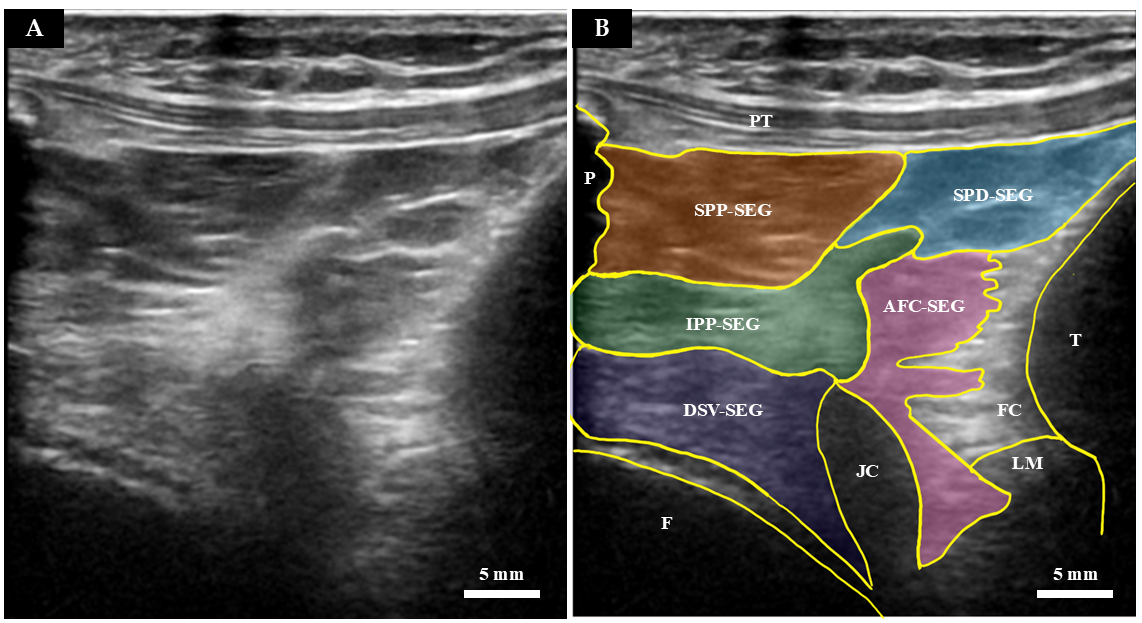

| Segment Abbreviation | Full Name | Macroscopic Anatomical Location | Histological and Structural Features |

|---|---|---|---|

| SPP-SEG | Superficial Proximal Segment | Connects the patella directly to the superficial layer of the patellar tendon. | Densely packed adipocytes. Separated from the SPD-SEG by connective tissue septa. |

| SPD-SEG | Superficial Distal Segment | Bounded by the patellar tendon, deep infrapatellar bursa, and tibia. | Adipocytes present. Linked to the tibia via the complex connective tissue of the joint capsule. |

| IPP-SEG | Infrapatellar Plica Segment | Regarded as the extended tissue of the infrapatellar plica (ligamentum mucosum). | High ratio of dense connective tissue mixed with adipocytes. Structurally less deformable. |

| DSV-SEG | Deep Synovial Segment | Deepest portion near the joint cavity. Separated from the patella by a horizontal cleft. | Characterized by a synovial cell lining on its articular surface. |

| AFC-SEG [Target Region] | Adipo-Follicular Segment | Bounded by SPD-SEG, IPP-SEG, and tibia. Connected to the anterior horns of the menisci. | Contains unique follicle-like spaces. Highly compliant and susceptible to joint pressure changes. |